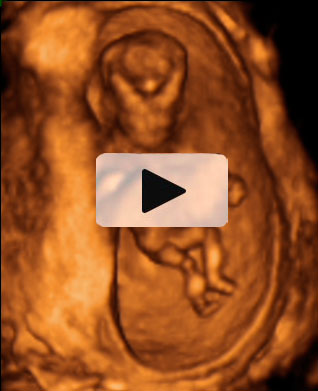

Ecografía Embarazo 2D y 3D Semana 12 - PLIEGUE NUCAL

Ecografía Embarazo 4D Semana 12 - PLIEGUE NUCAL